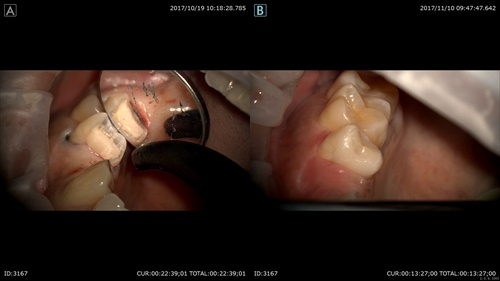

左が先日型取り前 右は本日セラミックセット